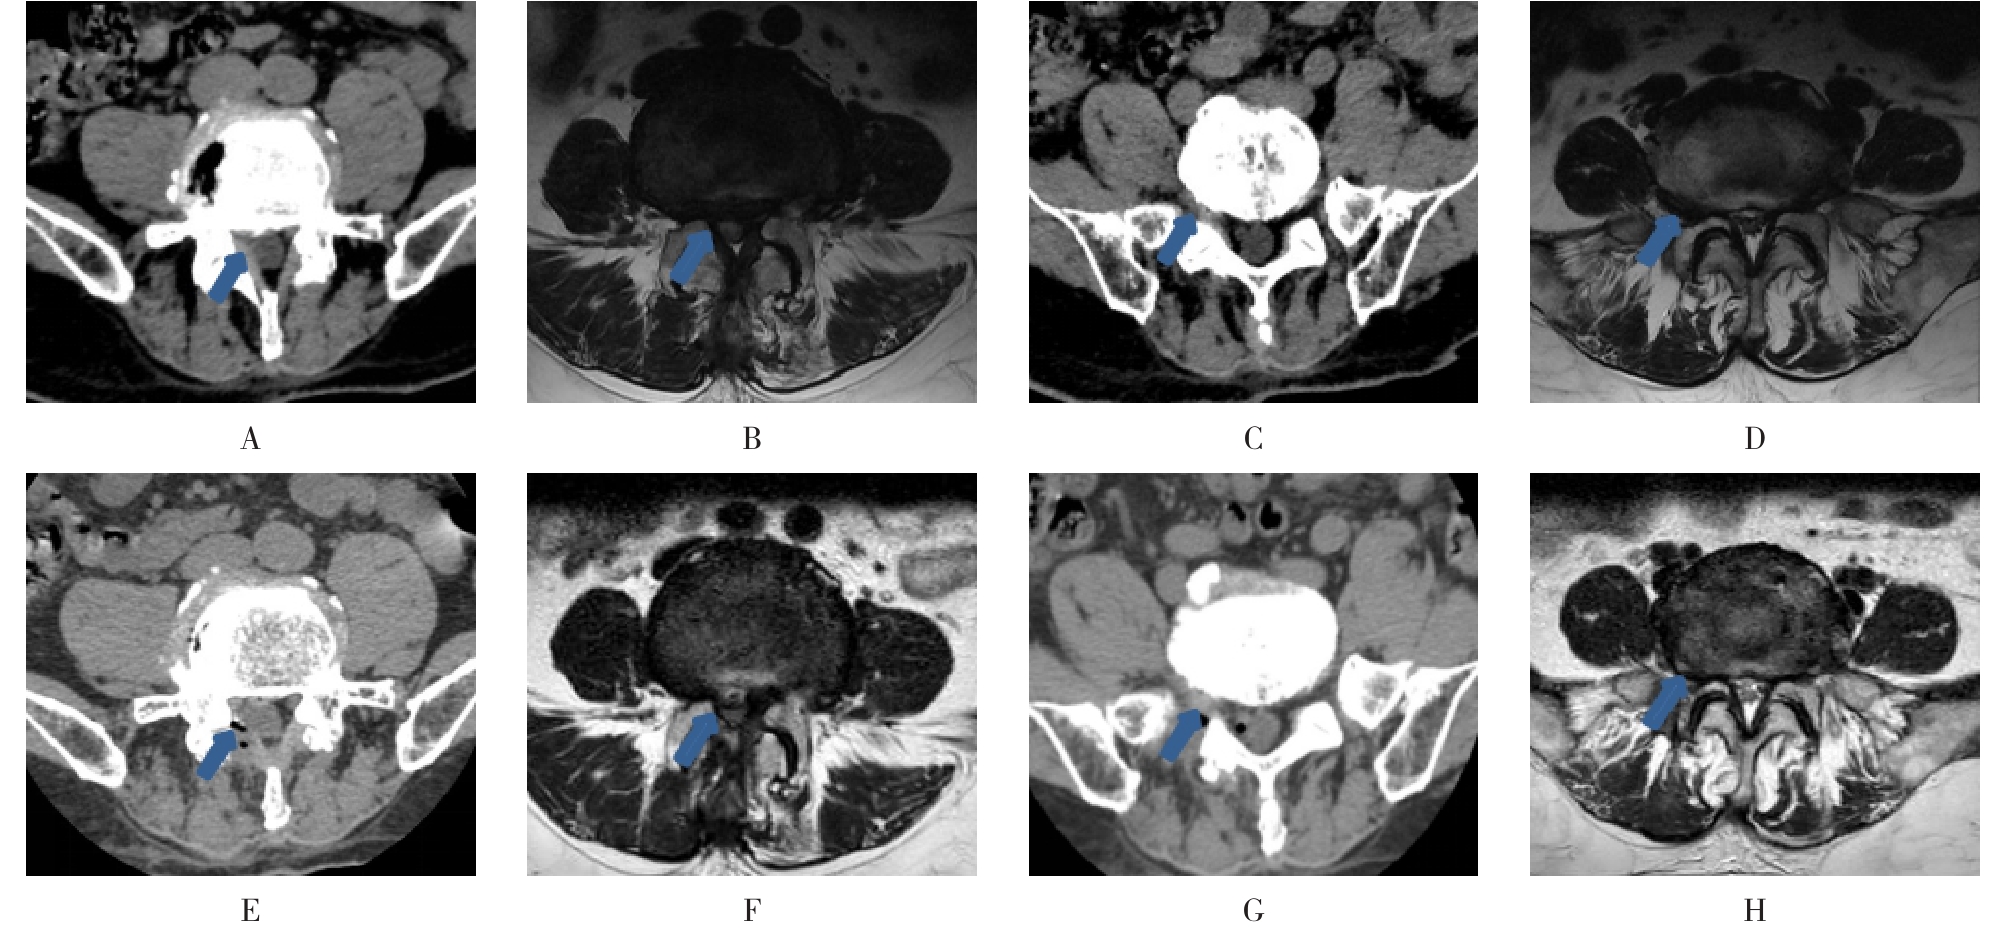

• 脊柱内镜侧后路联合减压术治疗腰神经根双卡综合征的临床疗效观察

2025, 31(12):25-32. DOI: 10.12235/E20250012

摘要 (122) HTML (46) PDF 10.14 M (90) 评论 (0) 收藏

摘要:目的 观察脊柱内镜侧后路联合减压术治疗腰神经根双卡综合征(DCS)的临床疗效、可行性、安全性和有效性。方法 回顾性分析2018年9月-2023年9月于该院就诊的50例腰椎退行性病变致腰神经根DCS患者的临床资料,根据手术方法不同,将患者分为观察组(37例)和对照组(13例)。观察组行脊柱内镜侧后路联合减压术治疗,对照组行非手术治疗。比较两组患者治疗前、治疗后1周、治疗后3个月、治疗后6个月和治疗后12个月的疼痛视觉模拟评分法(VAS)评分、Oswestry功能障碍指数(ODI)和日本骨科协会(JOA)评分。末次随访时,采用改良Macnab标准,评估临床疗效;采用腰椎MRI检查,评估椎间隙高度和椎间盘退变改良Pfirrmann分级。比较两组患者治疗的安全性(包括:并发症发生情况、复发情况和转手术治疗情况)。结果 50例患者均顺利完成治疗。两组患者术后VAS评分和ODI呈下降趋势,JOA评分呈升高趋势,观察组术后各时点VAS评分和ODI明显低于术前,且明显低于对照组,术后各时点JOA评分明显高于术前,且明显高于对照组,差异均有统计学意义(P < 0.05);观察组优良率为86.49%,明显高于对照组的76.92%,差异有统计学意义(P < 0.05);两组患者末次随访时,椎间隙高度和椎间盘退变Pfirrmann分级比较,差异均无统计学意义(P > 0.05)。两组患者围手术期均未出现神经损伤和脑脊液漏等严重并发症,观察组术后1例出现下肢放射性疼痛;观察组1例术后3个月出现腰椎间盘再突出;对照组有3例转手术治疗。结论 与非手术治疗相比,脊柱内镜侧后路联合减压术可更为安全、有效地缓解腰神经根DCS患者的疼痛,改善下肢功能,且早、中期临床疗效好。值得临床推广应用。